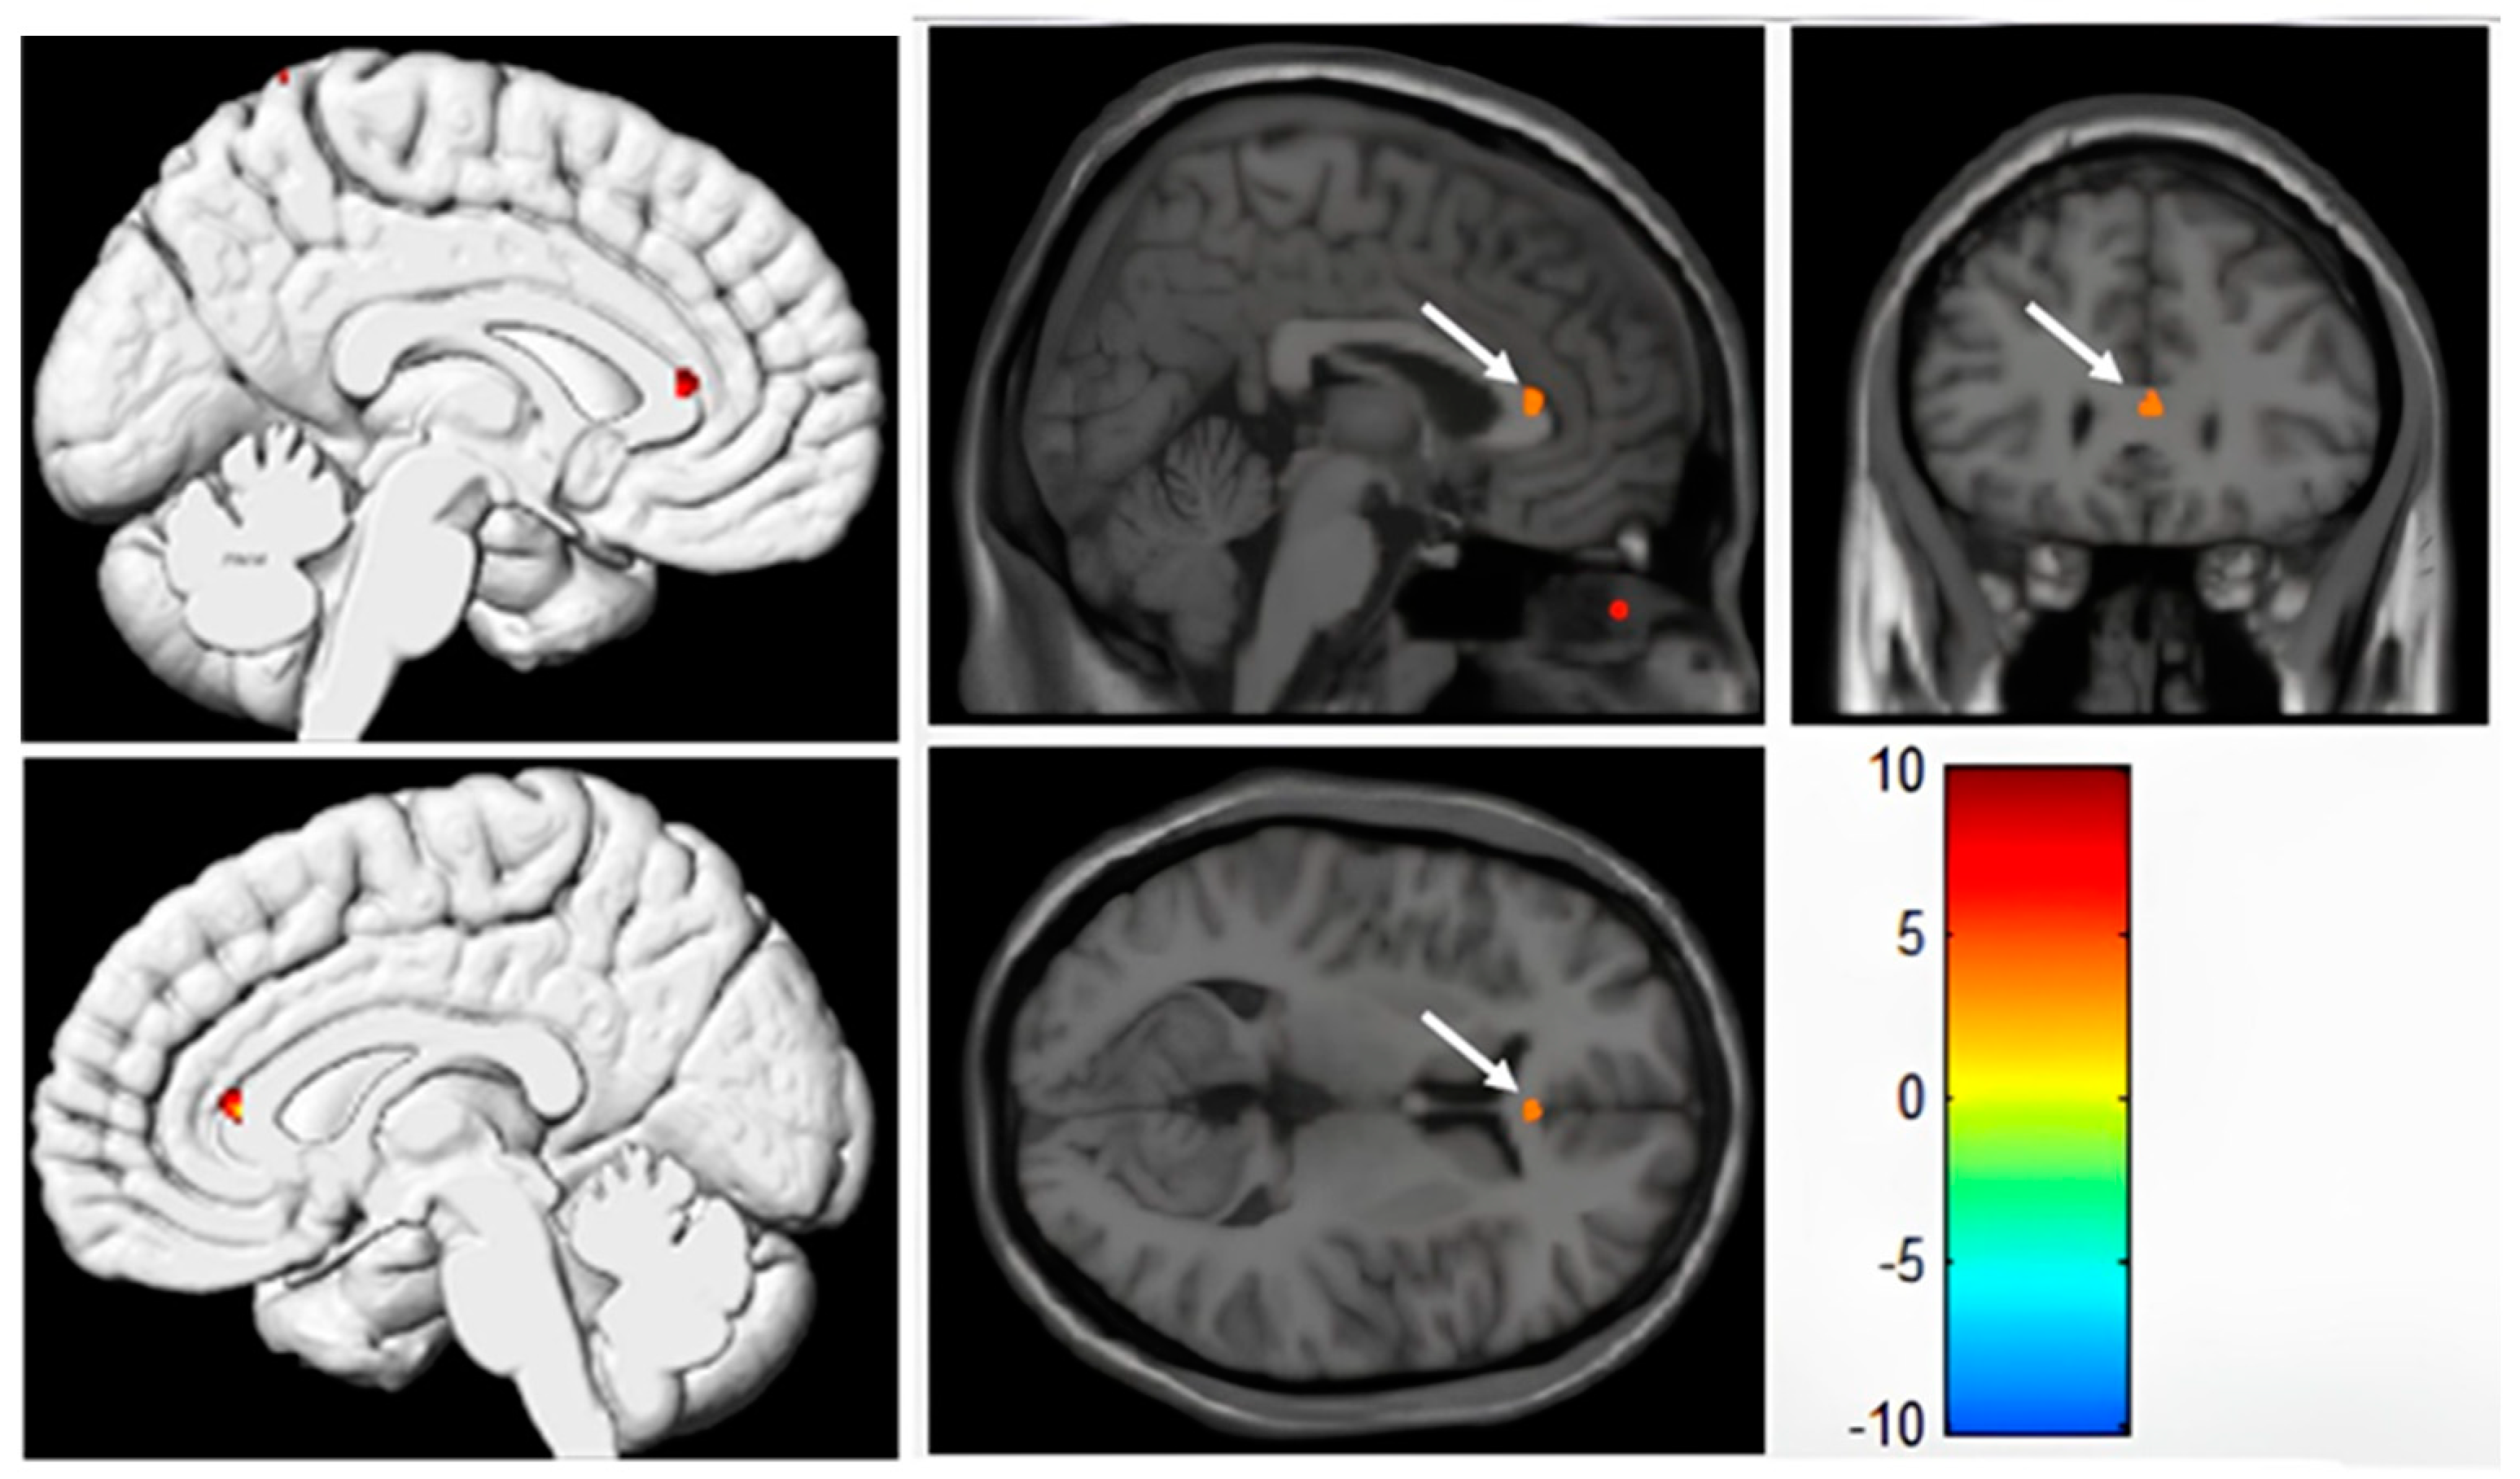

3.3. VBM Analysis of Cortical Grey Matter Based on 3D-T1WI

| Brain Area | Peak MNI Coordinate | Cluster Size | Statistical Value (T) | ||

|---|---|---|---|---|---|

| x | y | z | |||

| Right anterior cingulate gyrus | 3 | 30 | 9 | 11 | 3.5365 |